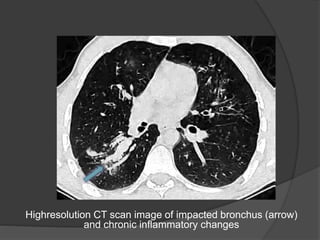

Highresolution CT scan image of impacted bronchus (arrow)

and chronic inflammatory changes